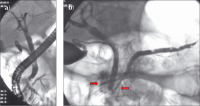

Abbildung 2: a) Die ERCP vom 15.3.2004 zeigt via die große Papille das normale Gallengangsystem und den Ductus Wirsungianus. b) Über die Minorpapille (→) wurde der im Kopfbereich schmale Ductus Santorini und der im Korpus leicht dilatierte Pankreashauptgang angespritzt. Im Bereich des Kopfes besteht eine leichte Kompression des Hauptganges (←).

Abbildung 3: a) Die ERCP vom 13.7.2005 zeigt via die Minorpapille die mittlerweile deutlichere Einengung des Ductus Santorini im Bereich des Pankreaskopfes und den konsekutiven Gangaufstau des Hauptganges (Ductus Wirsungianus). b) Bei weiterem Anspritzen des Ganges tritt Kontrastmittel in die später intraoperativ als nekrosehaltig identifizierte Pseudozyste über.